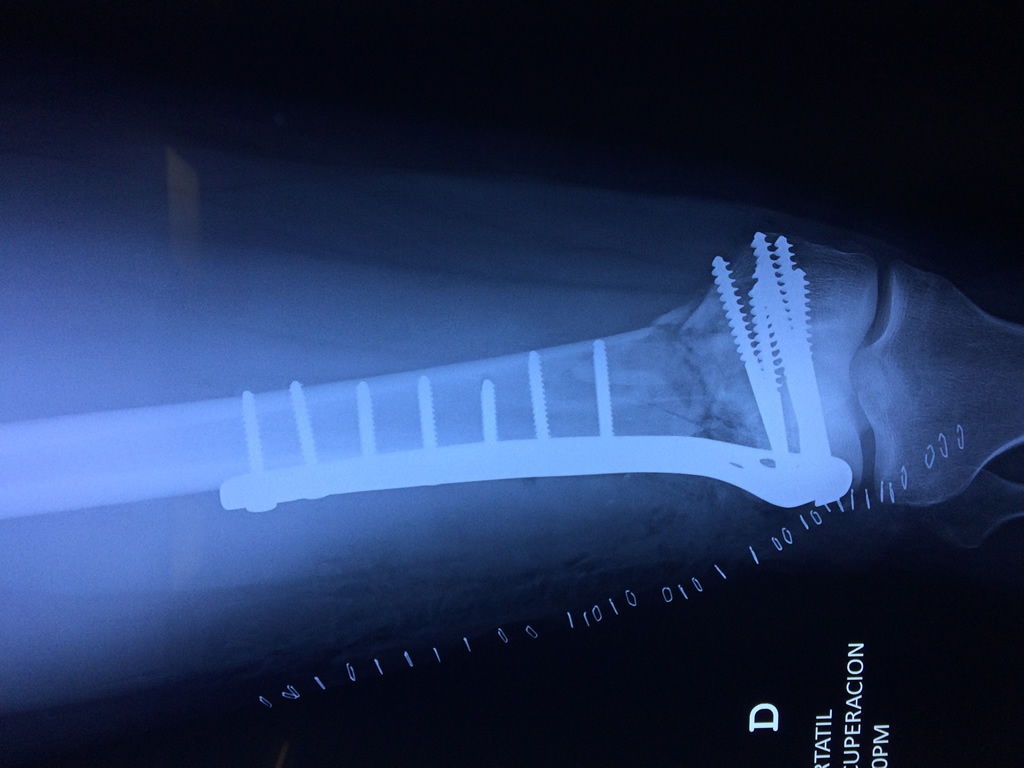

Húmero - Fémur